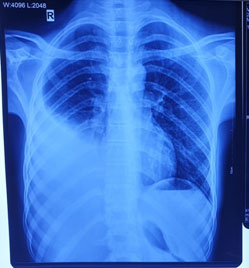

Pre operative X-Ray of Empyema